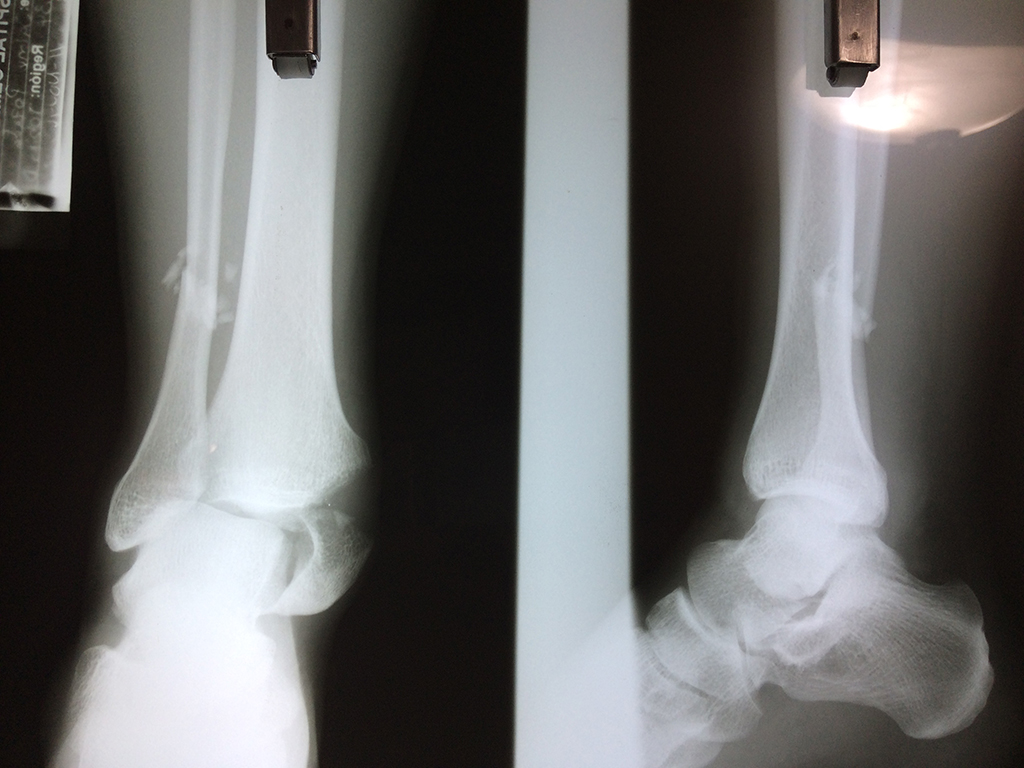

Una fractura de tobillo es la rotura de uno o más de los huesos del tobillo. Estas fracturas pueden ser:

- Parciales (el hueso está sólo parcialmente fisurado, no del todo).

- Completas (el hueso está perforado y está en 2 partes).

- Producirse en uno o ambos lados del tobillo.

Algunas fracturas de tobillo pueden requerir cirugía si:

- Los extremos de los huesos están desalineados entre sí (desplazados).

- La fractura se extiende hasta la articulación del tobillo (fractura intra-articular).

- Los tendones o ligamentos (tejidos que sujetan los músculos y los huesos entre sí) están rotos.

- El médico cree que sus huesos probablemente no sanen apropiadamente sin cirugía.

- El médico considera que la cirugía puede permitirle una recuperación más rápida y confiable.

- En los niños, la fractura involucra la parte del hueso del tobillo donde el hueso está creciendo.

Cuando se necesita cirugía, es probable que esta implique el uso de clavijas de metal, tornillos o placas para sostener los huesos en su lugar mientras la fractura se consolida. Los elementos de soporte pueden ser temporales o permanentes.